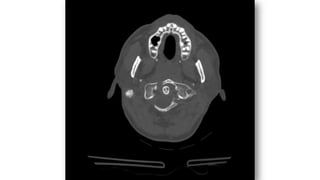

PARTES BLANDAS • Valorarhematoma por FX valorar espacios: • E. Nasofaríngeo (C1)=10mm • E. Retrofaríngeo (C2-C4)= 5-7mm • Retrotraqueal (C5-C7)= 22mm ó (< 1 cuerpo vertebral). Nasofaríngeo Retrofaríngeo Retrotraqueal